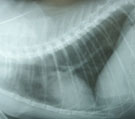

初診時胸部X線写真。肺野および心陰影に異常を認めず。 気管支鏡所見。LB2D1より白色円柱状物が飛び出してきたようにみえた。 同。RB4内にも同様の白色円柱状物がみえた。 白色物の細胞診標本。線毛上皮細胞、好酸球、杯細胞を含む粘液であった。

経過:初診時、身体検査にて発熱なく、心音・肺音に異常なし。CBCにて好酸数増加(2332/μl)、胸部X線写真にて肺野および心陰影に異常を認めず、糞便検査にて虫卵(−)、血液ガス分析ではpHa 7.43, Paco2 25 mmHg, Pao2 115 mmHg、A-aDo2 7.1 mmHgを示し異常なし。猫喘息が疑われたが感染・腫瘍・免疫疾患の鑑別と確定診断のため気管支鏡検査を行った。肉眼所見にて左右主気管支内に白色円柱状物が多数みられた。これはブラッシング細胞診にて、気管支粘膜上皮細胞、好酸球、杯細胞を含む粘液塊であることが分かった。末梢気道で形成され喀出された小粘液塊と考えられた。気管支肺胞洗浄液(BAL)[RB2, 10ml×3, 回収率90%]にて総細胞数の軽度増加(421/μl)、好酸球数の増加(26.75%)がみられた。BAL液の培養にて細菌も真菌も検出されなかった。以上所見より、猫喘息と診断された。同時に行った特異的血清IgEアレルゲン検査(92種)にて、羽毛、ハウスダスト、牛肉、卵、大豆、コーン、米、穀草、ジャガイモ、ビール酵母、マグロ、イワシ、カツオ、コットン、カポック、蚊に陽性を示した。診断後、去痰薬のみ(ビソルボン錠 2mg PO q12h)投与開始した。第21病日より食餌を変更しアレルゲンを除去し、空気清浄機などの室内環境も改善した。1週間後、咳は3−4回/週に減少し、第116病日に咳は完全消失した。現在1年3ヶ月経過しているが再発はみられない。